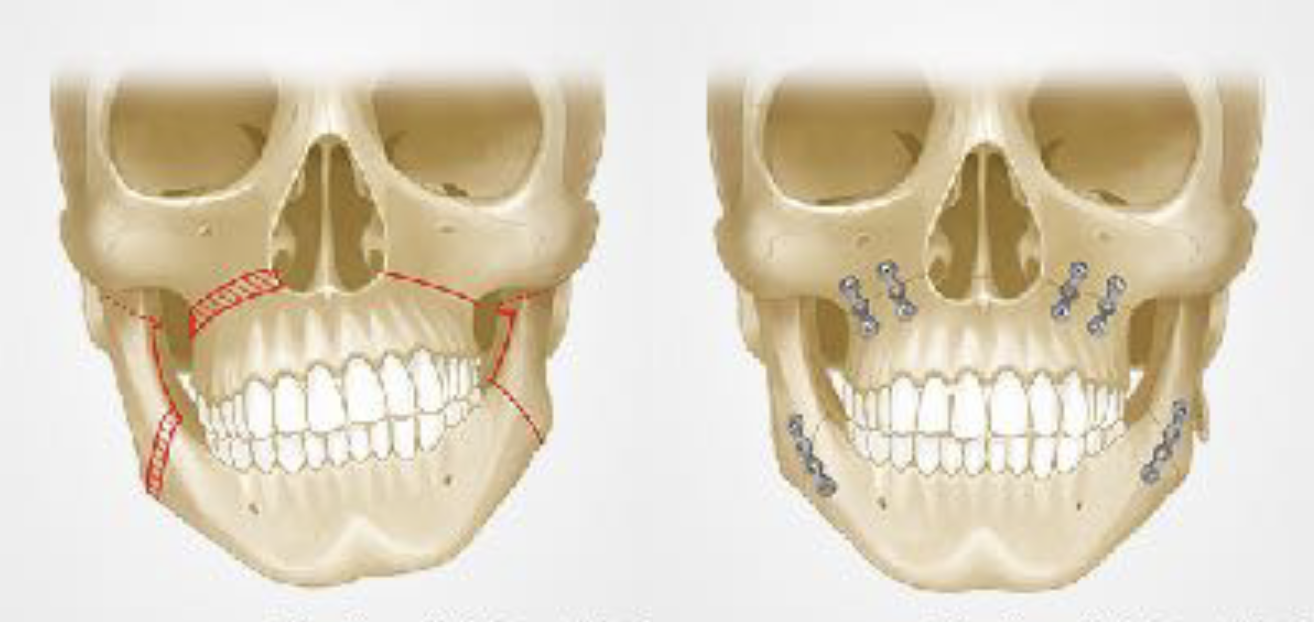

顎変形症とは、上下の顎の位置や形状に問題があり、かみ合わせが大きくずれている状態のことです。放置すれば咀嚼や発音がうまくできないほか、顎関節の痛みや不快感、お顔の歪みなど多くのトラブルにつながります。治療は外科矯正治療含む骨切りが必要となります。

当院では症状の改善と生活の質向上をめざし、適切な治療法をご提案いたします。

顎変形症

骨格について

骨格のバランスが良ければ機能的にも安定して、口元・顔貌が美しくなります。

左上図は受け口(下顎前突)の骨格(クラスⅢ)。

骨切り手術により下図のような上下顎がバランスのいい状態へ変化させることができます。

左上左図は受け口の逆で下顎が小さい骨格(クラスⅡ)。

SSROという骨切り手術によって上下顎のバランスを良くすることができます。

上顎骨が斜めに傾いてる症例も問題があります。

ルフォーという骨切り手術でゆがみを治すことができます。

上顎骨にルフォー、下顎にSSROを行ったイメージ図です。

骨格に問題があり、骨切り手術を行った方々の口元の変化です。

(左からクラスⅢ、クラスⅡ、上顎骨のゆがみ)